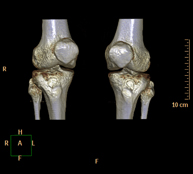

- Knee CT

Radiological examination based on an X-ray system and detectors that rotate around the patient, reconstructing the images by computer (multidetector computed tomography - MDCT) to study the bones, muscles and joints of the knees.